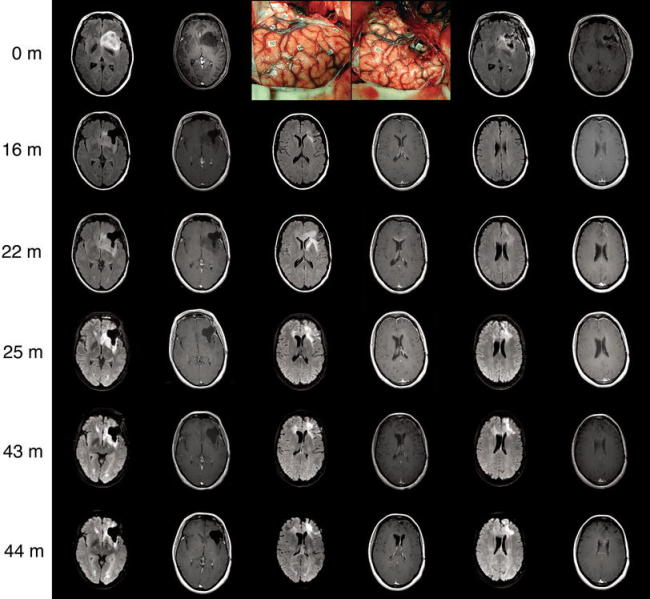

IDH1/2野生型胼胝體膠質(zhì)瘤的手術(shù)治療

IDH1/2野生型胼胝體膠質(zhì)瘤的手術(shù)治療,越來越多的作者發(fā)表的數(shù)據(jù)強(qiáng)調(diào)了切除胼胝體膠質(zhì)母細(xì)胞瘤的好處,特別是在不加重持續(xù)神經(jīng)功能障礙的情況下提高了總生存率。IDH突變是提高膠...